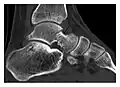

a

b

c

Figure 8: Proximal diaphyseal fatigue fracture of the tibia in a 20-year-old man with a history of regular jogging. (a) Lateral radiograph shows no obvious fracture lines but a subtle localized medial tibial cortex periosteal reaction (arrows). (b) Sagittal reformatted CT image acquired 1-month after the radiograph shows a linear hypoattenuation in the tibial cortex (arrowhead), as well as obvious periosteal thickening (arrows). (c) Sagittal T2-weighted fat-saturated image acquired the same day shows an area of hyperintensity spreading over the proximal tibia (arrows), which is consistent with the presence of proximal tibial fracture.[1]